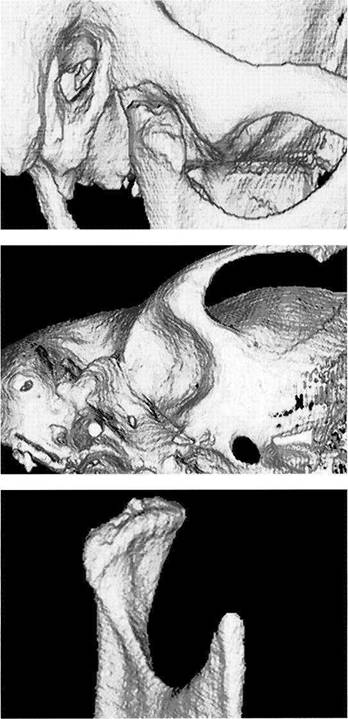

Computed Tomography of the Temporomandibular Joint and its Anatomical Correlation

CT is especially suited for representing the morphology of bone (Thompson et al. 1984, Westesson et al. 1987, Tanimoto et al. 1990, de Bont et al. 1993, Hu and Schneiderman 1995). Therefore, it is also employed for evaluating therapeutic measures (Fernandez Sanroman et al. 1998, Kawamata et al. 1998) and for planning implant procedures (Westesson 1996, Kraut 1998). However, on small structures with a high degree of curvature, such as the condyle and fossa, the so-called partial volume effect can cause one to overestimate the thickness of the cortical bone by as much as 200% (Ahlqvist and Isberg 1998). For investigating the disk, CT is

Lateral portion of the joint

A computed tomogram and a macroscopic anatomical prepara­tion of the lateral portion of a human temporomandibular joint. Left: Because the CT machine was not fitted with a soft-tissue win­dow, the soft tissues cannot be identified. The low thickness of the slice causes some of the marrow spaces to appear as cavities (ar­rows).

Right: Because in this specimen the insertion of the lateral pterygoid muscle lies farther lateral than usual, part of the tendon (outlined arrows) can be recognized.

Central portion of the joint

Pictures of the central portion of the same joint. Notice the precision with which the CT reproduces the contours of the osseous structures (arrows).

Medial portion of the joint

In addition to the contours of the fossa and protuberance, the cancel­lous bone of the condyle is promi­nently reproduced in the medial slice of the joint as well. The ability of CT to accurately reproduce the bony articular surfaces should not mislead one into thinking that CTs are absolutely necessary for all tem­poromandibular joint problems. They are practical for joint deforma­tions associated with syndromes, fractures, ankylosis, or tumors, but all other joint surface lesions can be adequately diagnosed through other clinical procedures (see also p. 68).